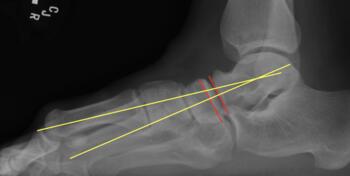

As the Ponseti grew in popularity, I noted significant discrediting of surgical options. Well long-term studies on the Ponsetti are starting to surface, and it is not without its own problems. Kids are lost to follow-up, not braced appropriately, and just like we saw in long-term studies with the posteromedial release, there is a lot of undercorrection. Casting cannot and will not ever achieve what the Cincinnati release can. Although the Ponseti may not have the complications of the Cincinnati, X-ray data reveals that the Ponseti cannot and does not correct everything, most critically, talocalcaneal angles. You can not solve a clubfoot with an Achilles tenotomy and an overly aggressive casting. As these kids develop, I see residual met adductus and calcaneal varus, along with casting complications like flat top talus and met primus elevatus. I then see that they will develop DJD just like posteriomedial and Cincinnati releases. Haasbeck and team in 1997 reported that the Cincinnatti required fewer procedures than the posteromedial release over the life of their study.14 Thomas performed a systematic review in 2019, concluding that the longer the study follow-up, the greater the relapse rate and the poorer the results of the Ponseti.15 For most of us who have done clubfeet surgery for many years, this is no surprise. Among the 46 studies meeting inclusion criteria, they saw as high as 67 percent required future surgeries to address relapse.15

Here is a typical case presentation. A 21-year-old Marine at Ft. Leonard Wood for training underwent a Cincinnati release at one year old and had stellar follow-up. Her surgeon even wrote her medical waiver for entrance into the Marines. She ran track in high school. She finished boot camp and completed all of her Marine training, but now has chronic pain. She no longer can run. She hasn’t passed her physical training in over a year. She developed talonavicular DJD. By all accounts, her overall clubfoot should be rated an A+; no residual deformity, normal talocalcaneal angles on AP and lateral views, no equinus, no residual varus, only slight met primus elevatus, but no signs of a flattop talus. Clinically, she lacks subtalar range of motion, which I commonly find post-clubfoot release of any kind. So many in the military do very well for a while, but the demands of the military eventually catch up to them. We all root for clubfeet to make it, but the odds are stacked against them.